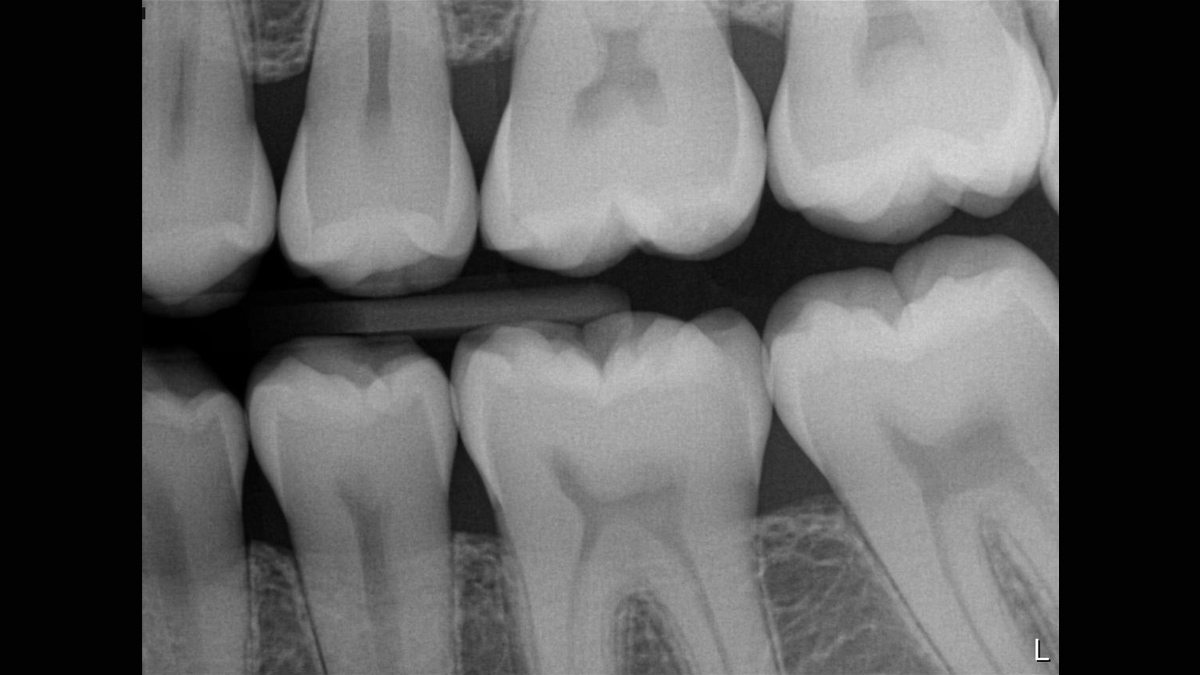

Excellent Images for Optimal Patient Care

Excellent image quality is just the beginning with the Xios XG Supreme intraoral sensor. With a number of enhancement options and the ability to easily adjust your images to support your individual preferences, you get more than just a sensor; you get an intraoral solution. Equipped with multiple sensor sizes, cable lengths, and connectivity options, you truly have a tool that adjusts to you, not the other way around.